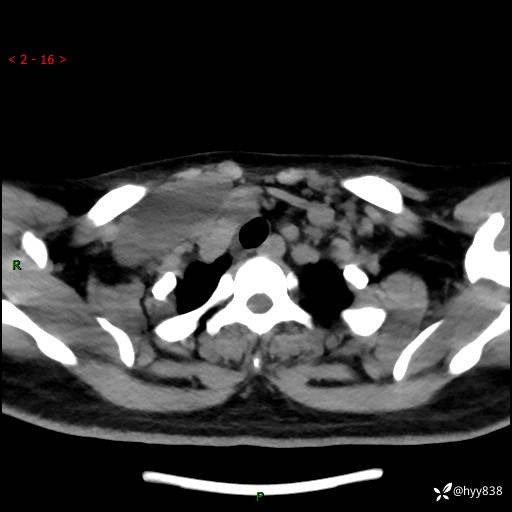

颈部CT平扫